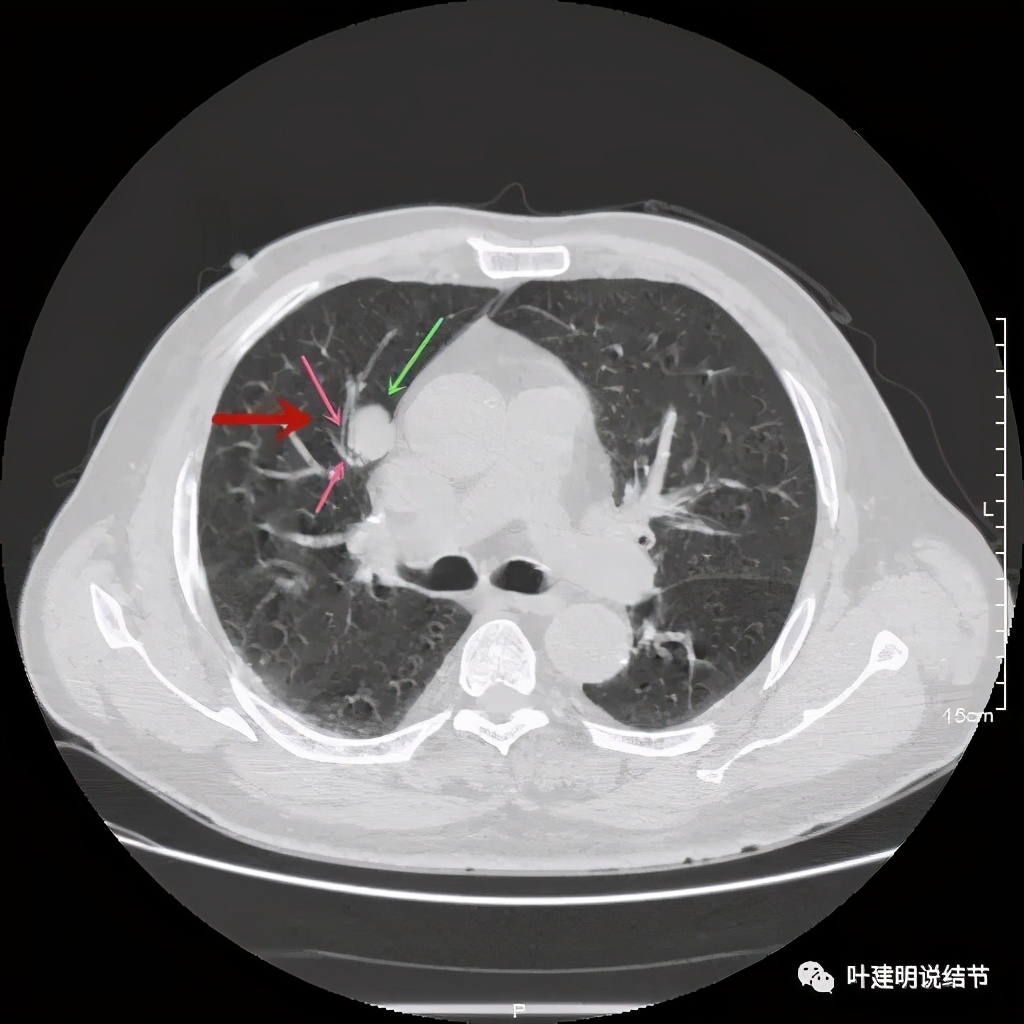

上图示病灶边缘过于光滑(绿色);局部有点状钙化(蓝色)

上图示病灶边缘过于光滑(绿色);血管贴边(桔色);

上图示病灶边缘过于光滑(绿色);血管贴边走行(桔色)

以上几图也示病灶边缘过光(绿色);血管贴边,感觉没受侵犯(桔色)